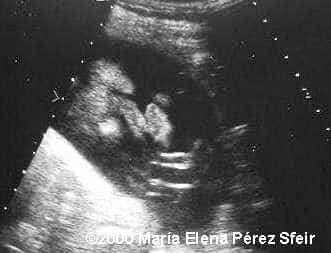

Cleft-lip, unilateral MarÃa Elena Pérez Sfeir, MD Article Published: May 30, 2002 Patagonia, Argentina This is an example of cleft-lip in a 3rd trimester fetus. Discussion Board Start a discussion about this article Add to Favorites Favorite